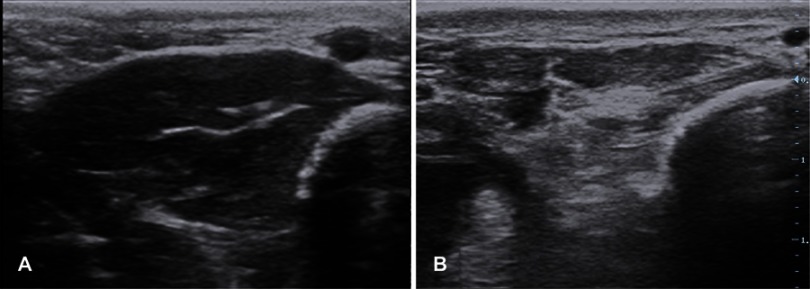

Amyotrophic lateral sclerosis (ALS) is a devastating neurodegenerative disorder characterized by dysfunction at multiple levels of the neuraxis. It remains a clinical diagnosis without a definitive diagnostic investigation. Electrodiagnostic testing provides supportive information and, along with imaging and biochemical markers, can help exclude mimicking conditions. Neuromuscular ultrasound has a valuable role in the diagnosis and monitoring of ALS and provides complementary information to clinical assessment and electrodiagnostic testing as well as insights into the underlying pathophysiology of this disease. This review highlights the evidence for ultrasound in the evaluation of bulbar, limb and respiratory musculature and peripheral nerves in ALS. Further research in this evolving area is required.